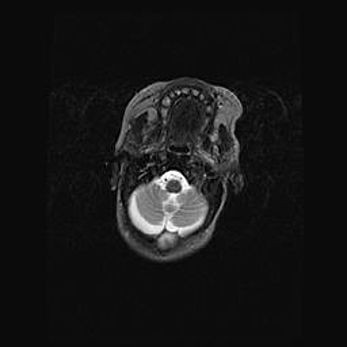

Лейкомаляция с кистозно-глиозной дегенерацией головного мозга.

Возраст: 2 месяца 25 дней

Вес: 6400 г

Окружность головы: 40 см

Срок гестации: 41 неделя

Лейкомаляцию относят к ишемически-гипоксическим повреждениям головного мозга, диагностируемым у новорожденных. При лейкомаляции в головном мозге обнаруживают очаги некроза, возникшие после тяжелой гипоксии и нарушения кровотока. В процессе морфогенеза очаги проходят три стадии: 1) развития некроза, 2) резорбции и 3) формирования глиозного рубца или кисты. Перивентрикулярная лейкомаляция (ПЛ) встречается примерно в 12% случаев среди новорожденных, обычно – у недоношенных детей, причем, частота ее зависит от массы, с которой младенец появился на свет. Наибольшее число малышей страдает лейкомаляцией, если масса при рождении 1500-2500 г.